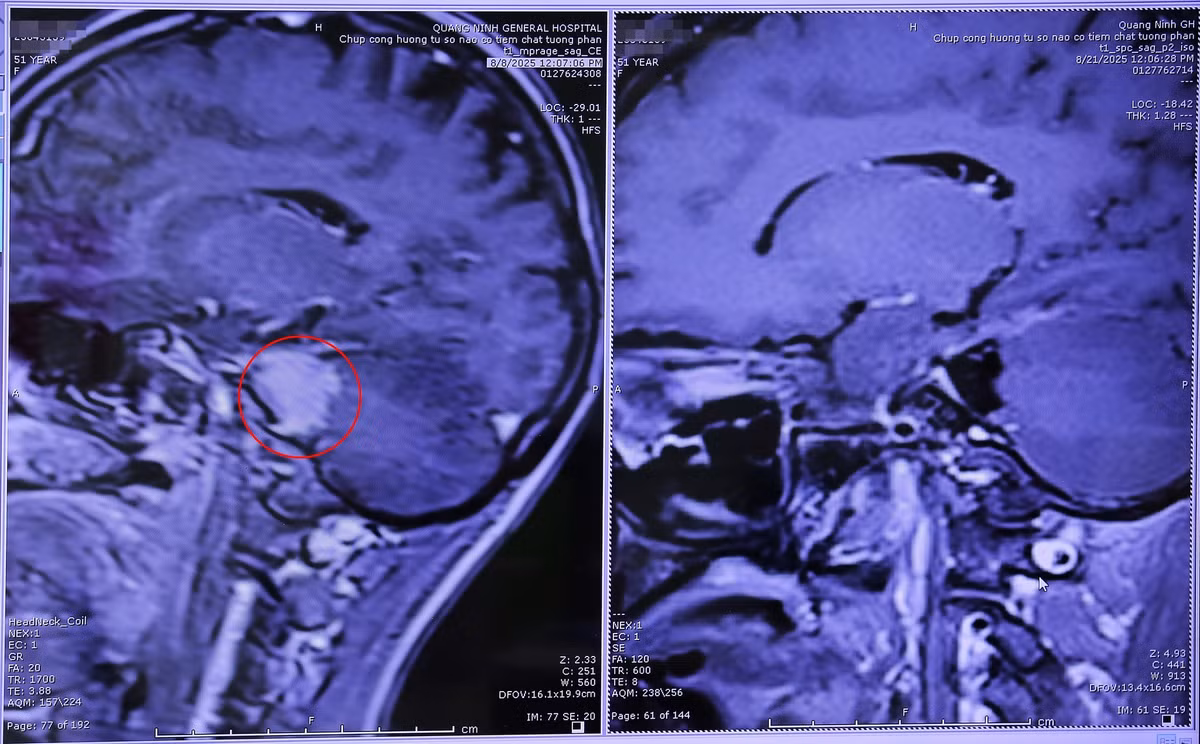

Trường hợp đầu tiên là bệnh nhân T.X.M (51 tuổi, xã Đầm Hà, tỉnh Quảng Ninh) ở nhà xuất hiện đau đầu, đau mặt do chèn ép dây thần kinh số V bên phải. Kết quả chụp MRI cho thấy, bệnh nhân M. có khối u màng não góc cầu tiểu não bên phải, kích thước 3x1,5cm, chèn ép cầu não, bọc quanh phức hợp thần kinh 7,8, chèn ép dây thần kinh số 5 và phức hợp thần kinh 9,10,11.

Bằng kinh nghiệm và sự hỗ trợ của kính vi phẫu, các bác sĩ ngoại thần kinh đã thực hiện phẫu thuật vi phẫu bóc tách thành công khối u màng não góc tiểu cầu phải cho bệnh nhân M, bảo tồn cấu trúc mạch máu thần kinh.

khoiugoctieucaunao-1.jpg

u-nao-3.jpg

Hình ảnh chụp cộng hưởng từ khối u màng não góc cầu tiểu não phải được phẫu thuật lấy bỏ toàn bộ - Ảnh BVCC